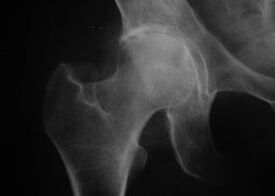

Coxathrose, Arthrose des Hüftgelenks

Bei dieser Erkrankung wird ein klassisches Krankheitsbild der Arthrose beobachtet.

Das erste Symptom einer Coxarthrose sind Beschwerden im Hüftgelenk nach körperlicher Aktivität.

Bei fortschreitender Coxarthrose nehmen die Schmerzen zu, es kommt zu Steifheit und eingeschränkter Beweglichkeit.

Patienten mit einer schweren Form der Coxarthrose schonen das betroffene Glied, vermeiden es, darauf zu treten, und wählen im Stillstand Positionen, in denen der Schmerz am wenigsten spürbar ist.